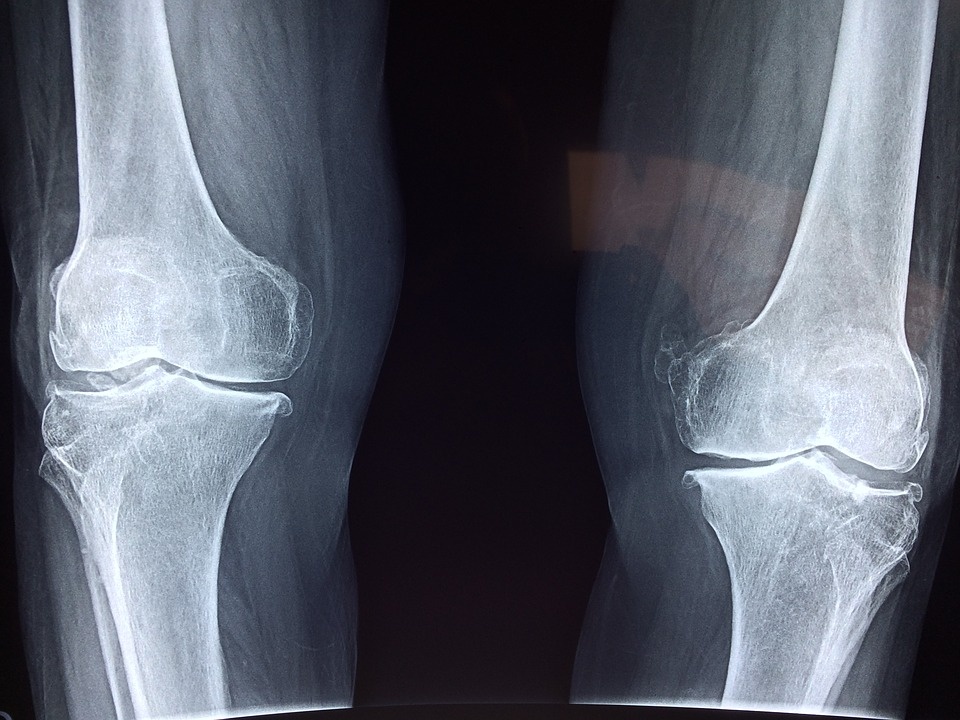

患通常儿四肢短小,身材矮小。肢体或身体其他部位的骨骼畸形可能包括每只手的第一根骨头,通常比异常短的手指更短,而且手指某些骨头之间的关节也可能融合(交叉),导致行动能力下降。足畸形也可以由每根脚骨头的异常融合引起。部分或完全脱位的身体某些关节也很明显。有些情况下,他们还容易发生骨关节病,导致疼痛,压痛,僵硬或某些关节畸形。

骨质异常可发生在脊柱,如颈椎椎骨闭合不全等。他们产生反常的侧弯和前后弯曲的脊柱。部分患者出现关节部分脱位,导致脊髓受压。听觉通常是正常的,但可能会因中耳三根细小骨头的不正常融合造成听力损害。头和脸的其它畸形包括高突出的前额,异常小的下巴,高弯曲的腭和腭裂。它们可能会发展成威胁生命的并发症,还可能出现呼吸道阻塞和呼吸窘迫。纵裂发育不良的症状和表现被认为是由于不正常的软骨形成所致,从而影响骨骼发育。一般胚胎发育初期,骨骼主要由软骨构成,软骨逐渐被骨化所取代。生下来之后,很多骨骼仍然主要由软骨构成,最后变成骨质化。